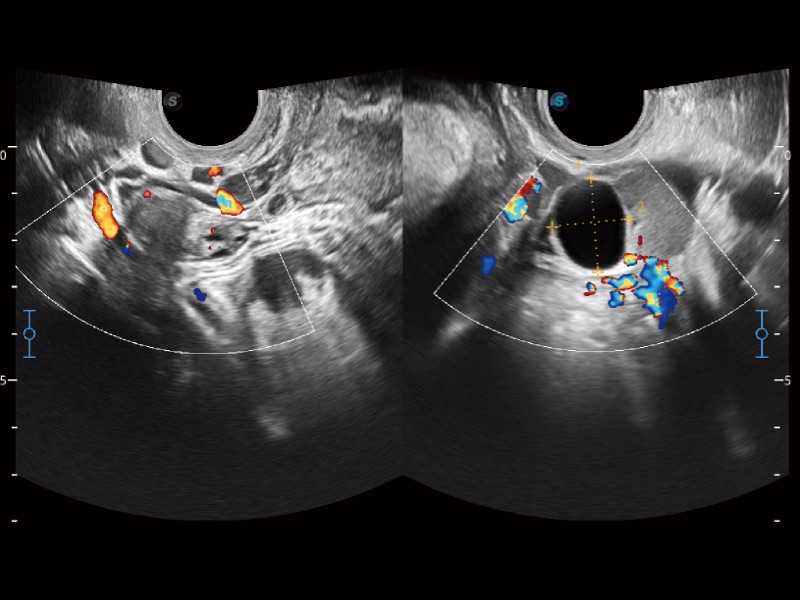

妇产科应用

高分辨率血流成像技术提高了对低速血流信号的检测能力。在提高空间分辨率的同时,也克服了血流外溢现象,为用户提供更加真实的血流动力学信息。